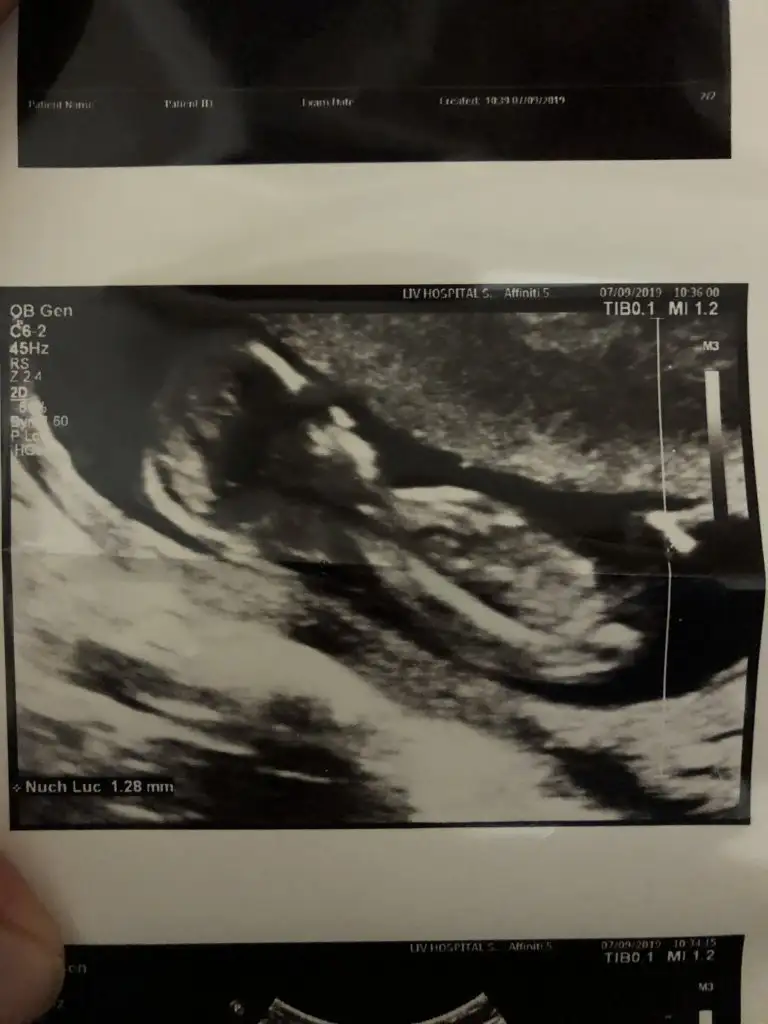

13+4 nub olmaz 11 yada 12 hafta olmalı kafa şekli kız ama tutmaya bilirMerhaba benim için de anlayan birisi tahminde bulunabilir mi? 13+4 haftalık hamilelik.

Teşekkür ederim cevap verdiğiniz için. Eve gittiğimde daha eski ultrason görüntüsü var mı bakıp yükleyeceğim. Doktor da kıza benziyor dedi fakat çok da net değil biraz daha bekleyelim dedi. Ben de merak ediyorum.13+4 nub olmaz 11 yada 12 hafta olmalı kafa şekli kız ama tutmaya bilir